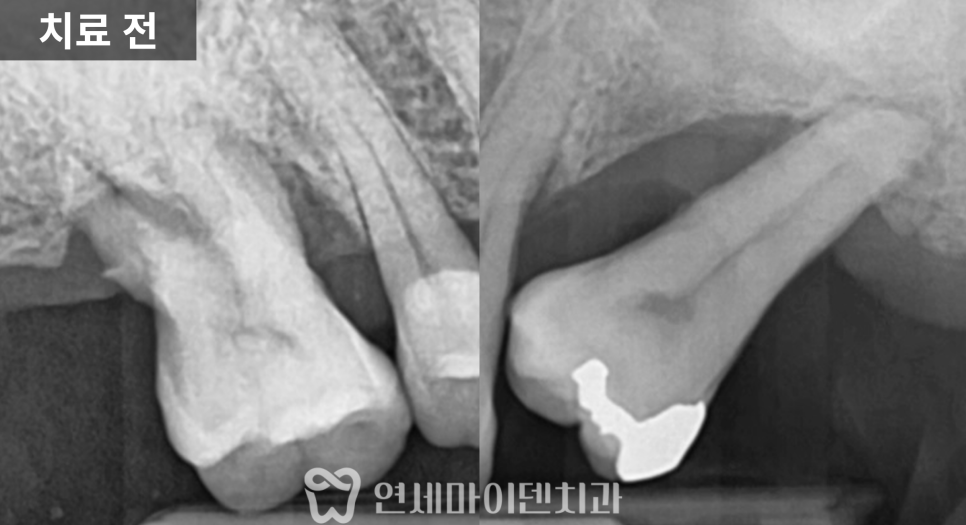

치료 전 방사선 사진을 보면

치아가 쓰러진 문제도 있었지만

무엇보다 뼈의 폭과 높이가

많이 줄어든 상태

였습니다.

잇몸도 전반적으로 약했고,

1차 수술: 발치, 염증 정리, 식립과 이식 동시 진행

첫 단계에서는

아래 1개, 위 2개

3개의 임플란트를 계획했습니다.

위쪽은 상악동이 내려와 있어

상악동 거상술과 뼈이식을 함께 시행한 뒤

그 공간에 임플란트를 식립했습니다.

아래쪽은 뼈 상태가 비교적 유지되어 있었지만

안정적인 고정을 위해

필요한 부위에 뼈이식을 병행했습니다.